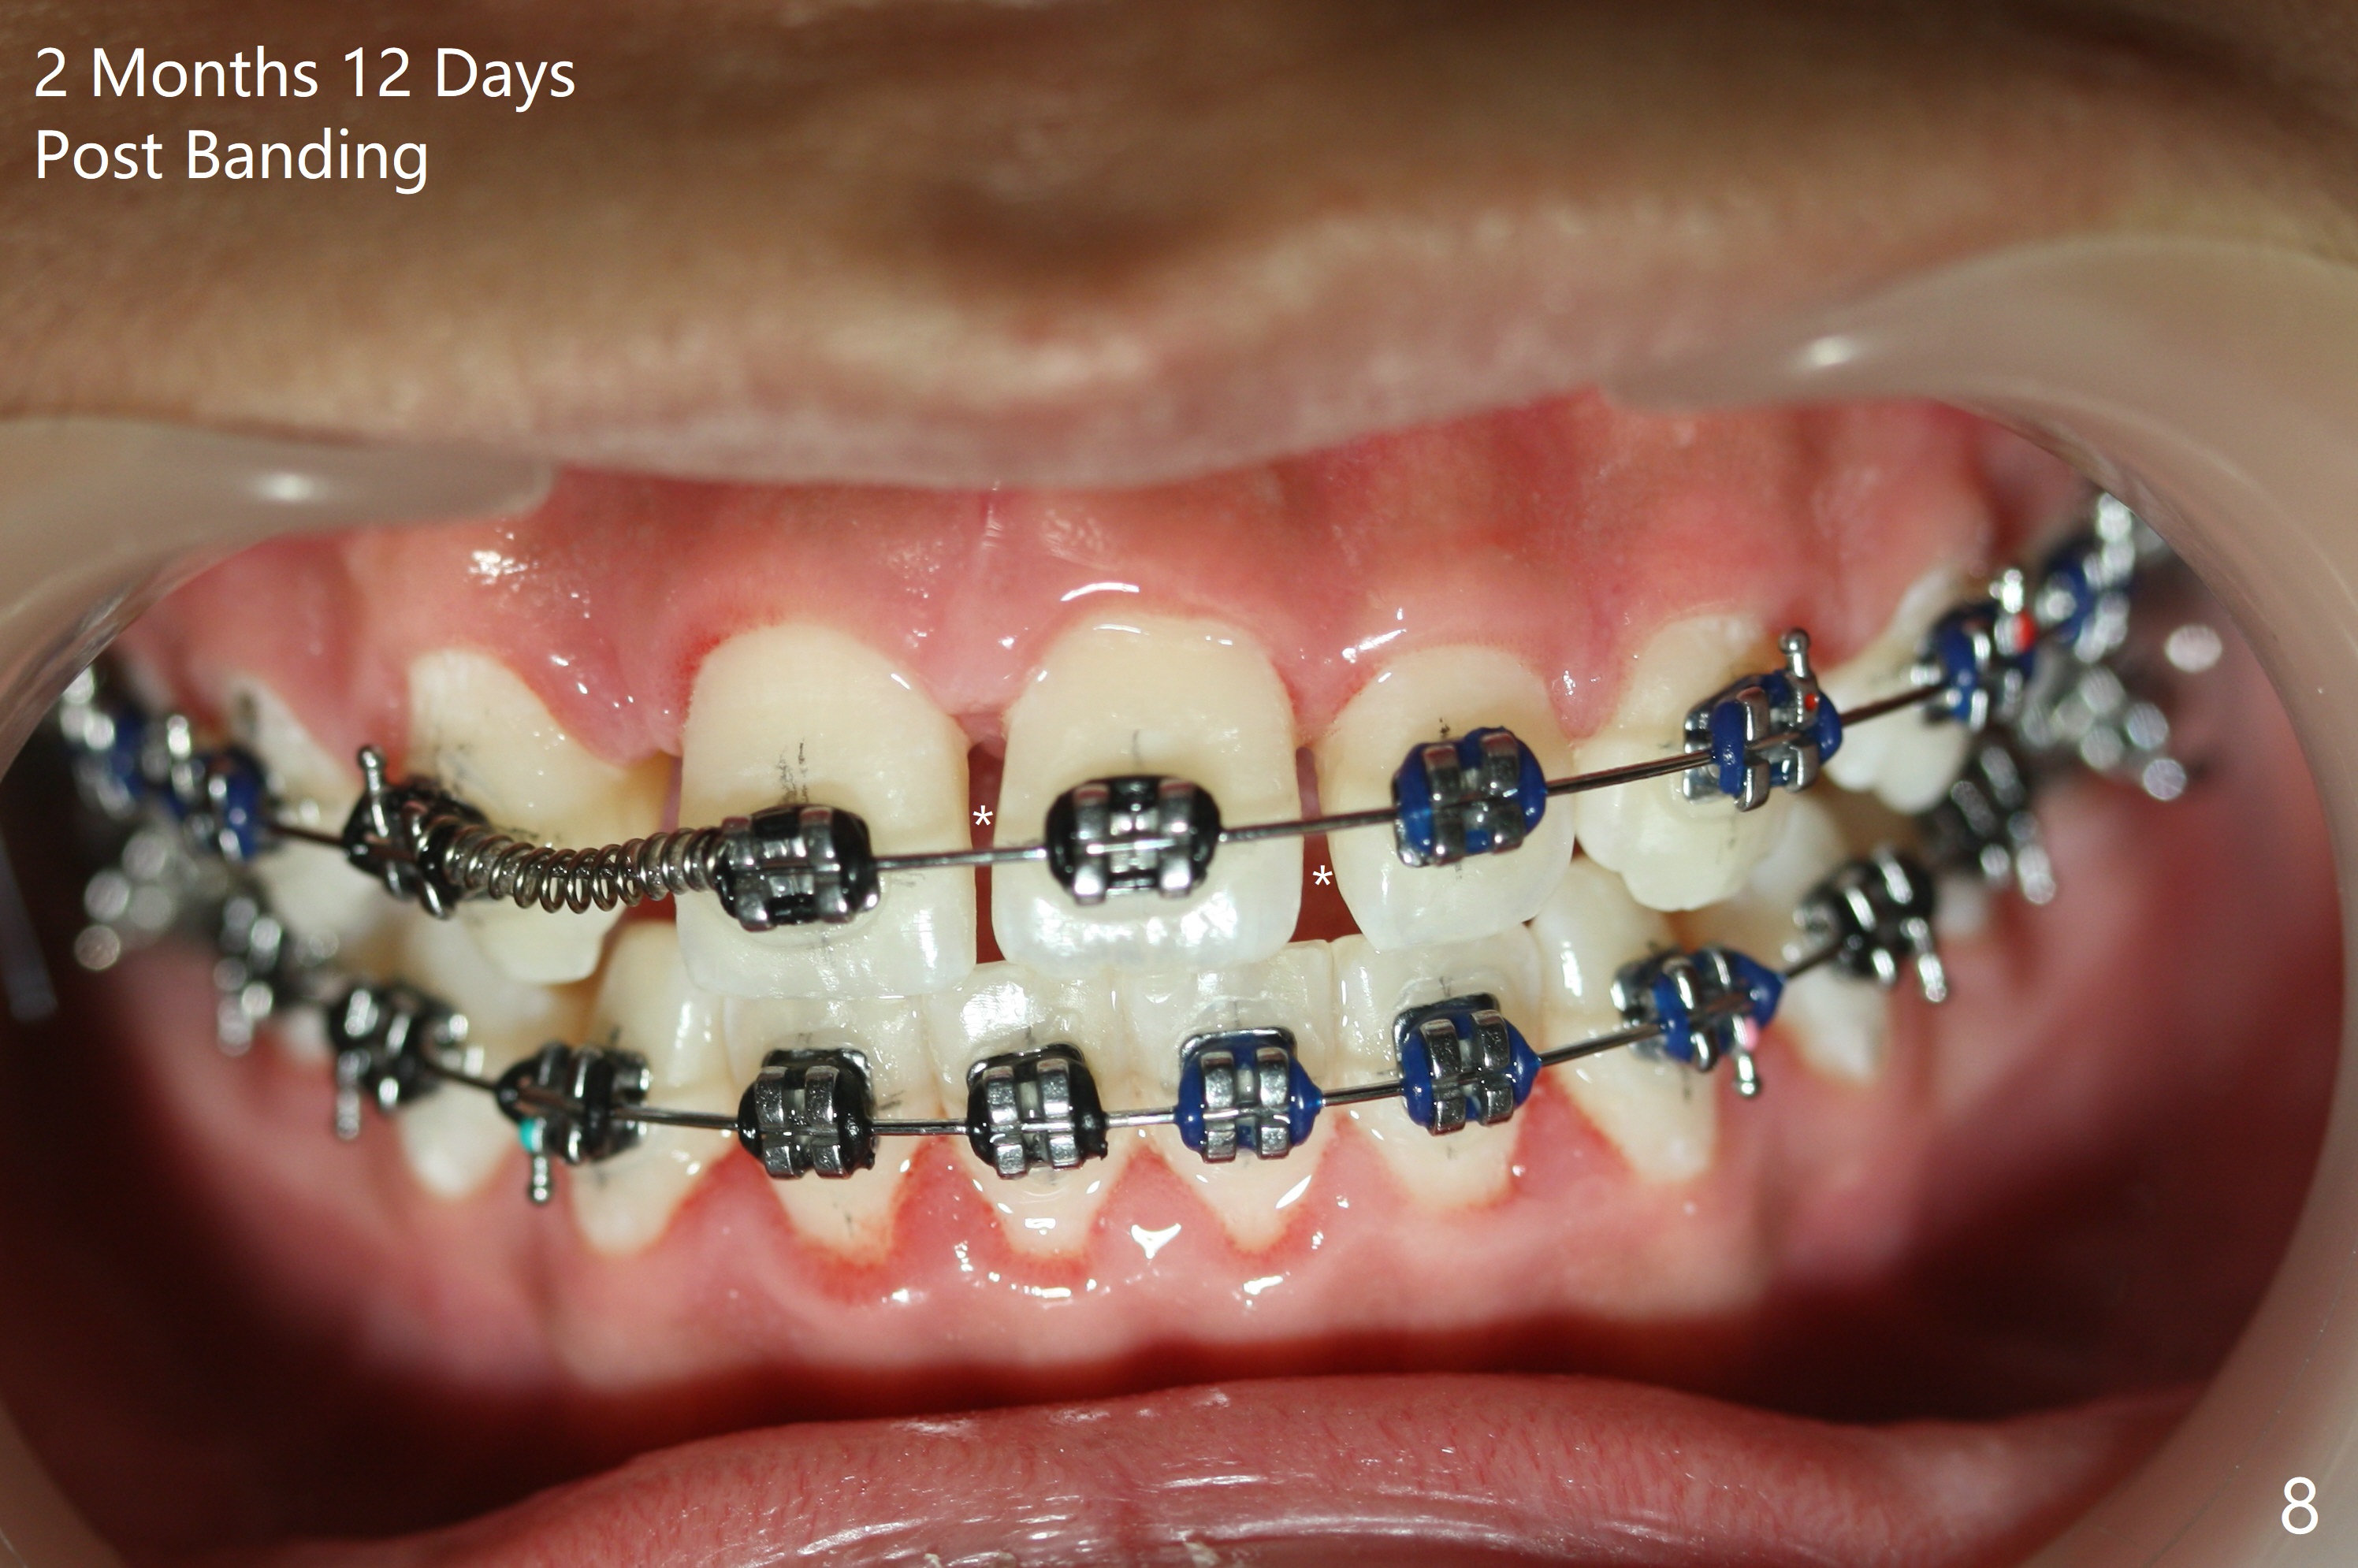

Preop cephalometric tracing shows normal skeletal relationship (Fig.1,2). The upper dental midline deviates to the right (Fig.3). To control root torque, UR1,3 bracketing is intentionally placed off (Fig.4,5, as compared to Fig.6). Take PA for UR1/3 next visit. In fact PA has not been taken. The patient has complained of UR1 turning (mesial incisal edge elongation due to bracket off placement) since the 1st appointment post banding. On the 3rd appointment (2 months 12 days post banding with 18 ss wire), the mesial incisal edge of UR1 and the distal incisal edge of UR3 are trimmed; 18 wires are reused with addition of an open coil spring between UR1-3 (Fig.7). Extra diastemata have appeared mesial and distal to UL1 (Fig.8 *), creating room to correct the upper dental midline shifting. PA is taken 5 months post banding (Fig.9). The roots of neighboring teeth are parallel with new bone formation behind. The mesiodistal space is similar to that of the tooth #10 following consolidation of diastemata on the left. More space is gained 12 months post banding (Fig.10).